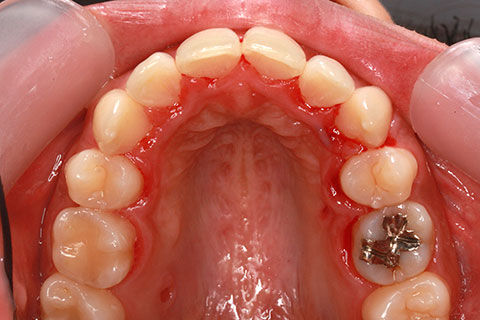

治療前

治療中(開始直後)

治療中(開始半年後)

治療後

- 年齢・性別

- 25歳女性

- 治療期間

- 2年0ヶ月

- 抜歯

- 上下4番抜歯

- 治療費

- 110万円

- 治療内容

- 施術の副作用(リスク)

- 表側矯正と比較して、力学的な操作性が複雑なため、ボーイングエフェクトを起こしやすい。